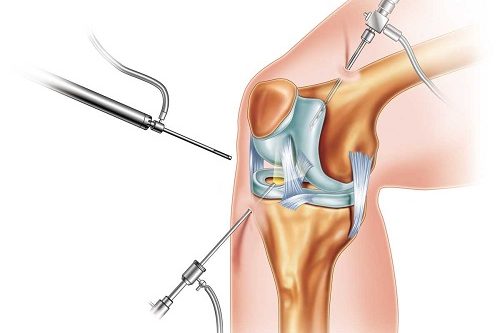

Diz Artroskopisi Nedir? Diz artroskopisi, diz bölümlerinin iç bölümünün küçük bir kamera (artroskop) ile girilerek yapılan cerrahi bir işlemdir. Bu işlem, iç dizinin daha ayrıntılı ve tedavisi için kullanılır. Artroskop, cerrahın dizinin içindeki yapıların net bir şekilde görülmemesini sağlar. Amacı ve Hedefleri Tanısal Amaç : Dizdeki kesin teşhisini koymak için kullanılır. Bu, menisküs yırtıkları, bağ…